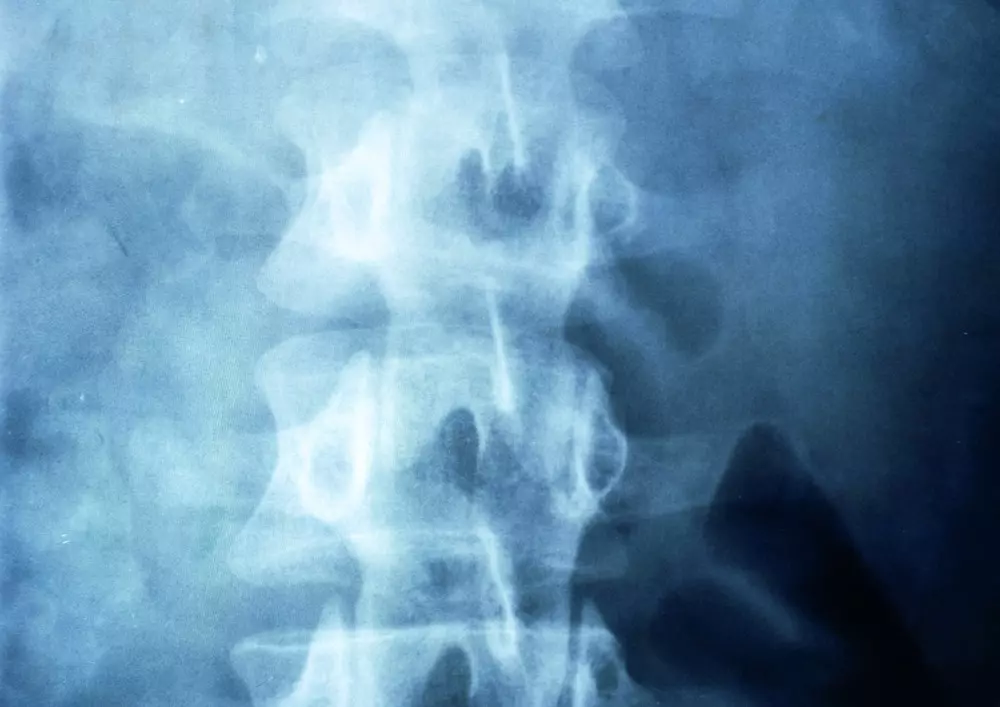

Temat numeru osiemdziesiątego wydania „Praktycznej Fizjoterapii i Rehabilitacji” brzmi „Trening funkcjonalny seniora jako alternatywa chirurgicznego leczenia choroby zwyrodnieniowej stawów kończyn dolnych – analiza przypadku”. Endoprotezoplastyka to bardzo inwazyjna metoda, która nie zawsze jest możliwa do zastosowania. Istnieją jednak metody zachowawcze, których właściwa kombinacja umożliwia powrót do sprawności i pozbycie się bólu. Jedną z nich jest właśnie trening funkcjonalny, który omawiamy w aktualnym numerze.